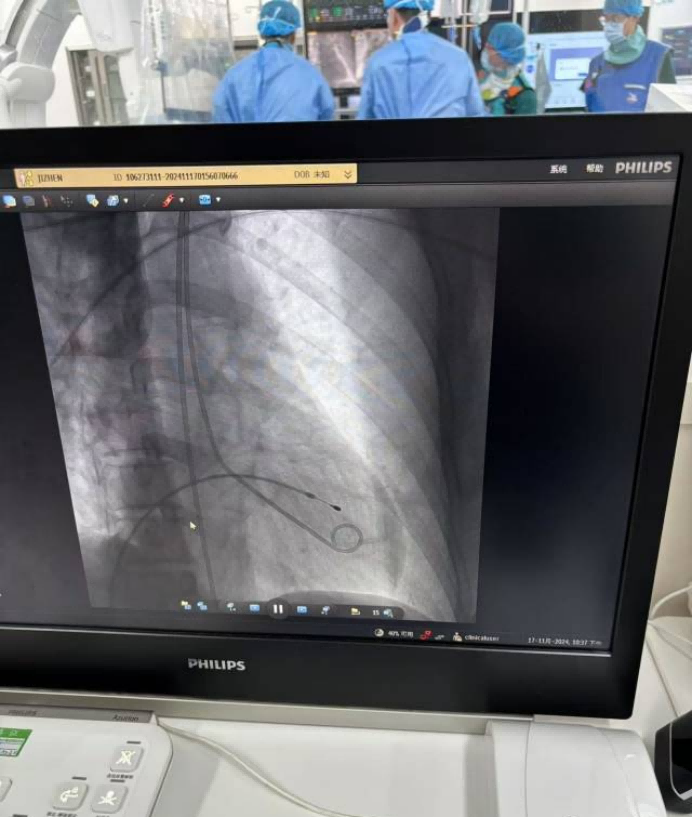

成功植入臨時起搏器和啟用 IABP,患者血壓逐漸穩定,心律失常得到控制。